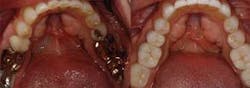

Full arch, occlusal images, as part of a photographic series, are an important adjunct to the new-patient examination. Images of only one or two teeth, such as those commonly captured with an intraoral camera, center on single-tooth dentistry but do little to help clinicians, staff, or patients think about patient needs in a comprehensive fashion (Fig. 1). The way clinicians evaluate and communicate with patients should be in alignment with the way they wish to treat their patients. Patients can better understand their needs when they can clearly see the "big picture." Full arch, occlusal images are an excellent way to help patients see the big picture and should be part of any new-patient examination (Figs. 2 and 3).

For patients to proceed with treatment in a comprehensive way, they must feel confident in our ability to deliver care. There are multiple methods of demonstrating capability to patients — clean and tidy offices, pleasant, long-term staff members, and patient testimonials. However, I have found that sharing photographs of restored arches that demonstrate the transformations possible with modern materials and techniques is very effective (Figs. 5 and 6; 7 and 8). Just as everyone appreciates how restorative dentistry can improve a person’s smile, patients also appreciate how posterior dentistry can improve a deteriorating situation — especially when the preoperative case reflects their own needs.